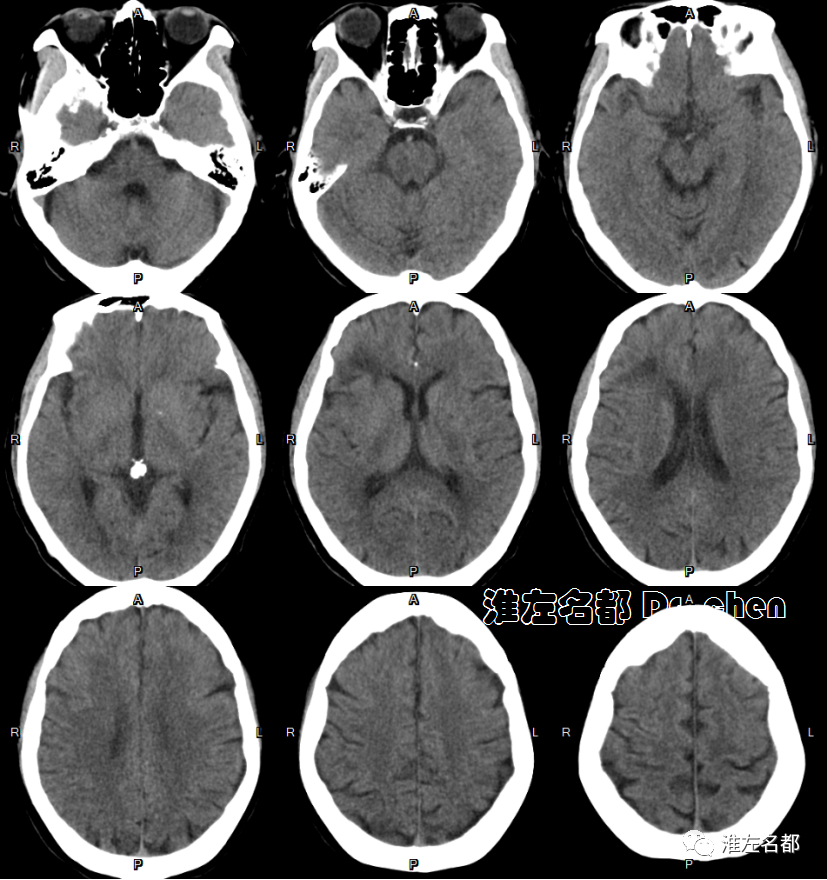

△头颅CT平扫:右侧额叶陈旧性梗死,左侧胼胝体膝部和临近脑组织低密度。